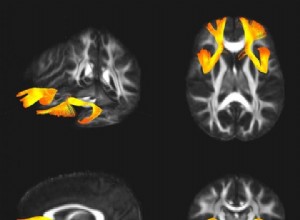

Entraîner l'attention réduit l'activité cérébrale : une étude fascinante de l'Université de Californie